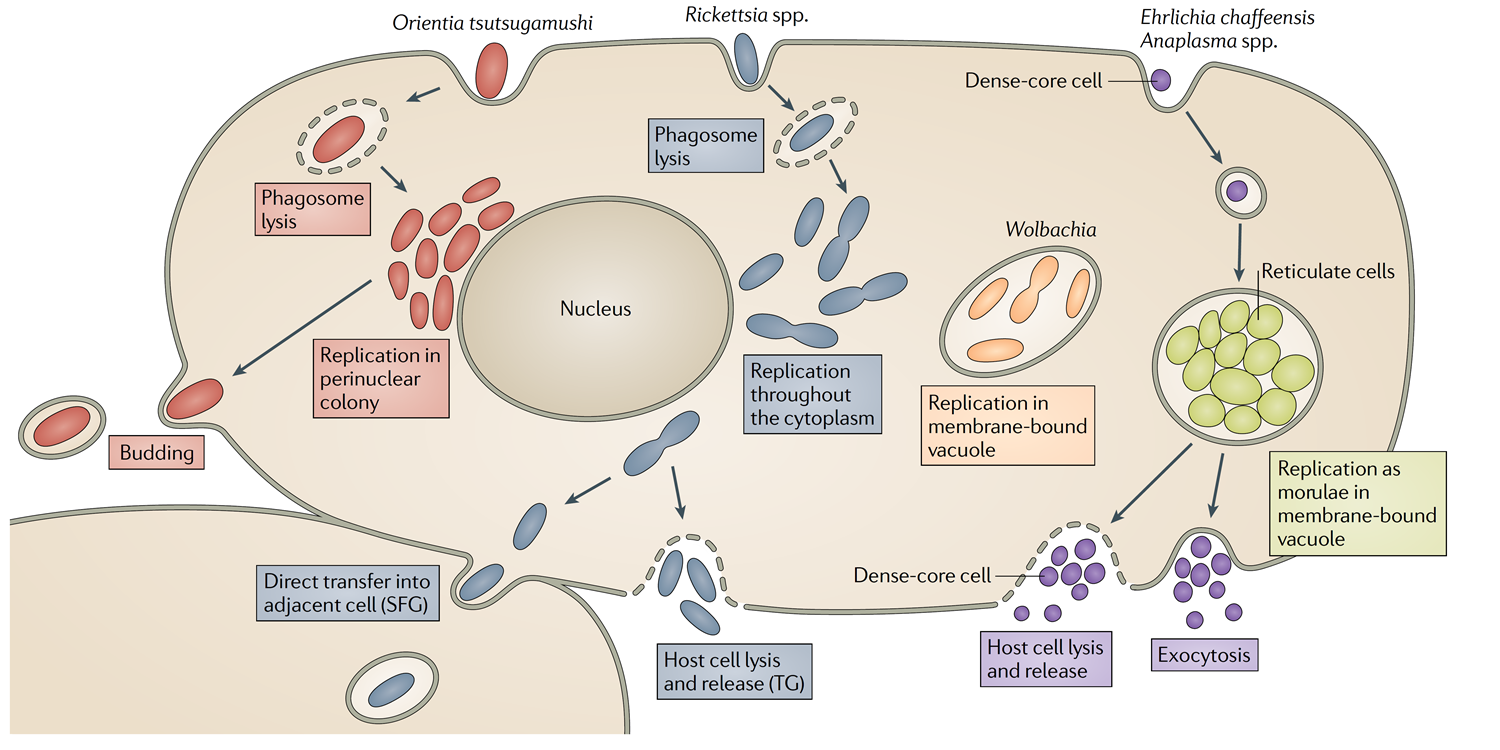

Rickettsia (立克次體)

- 絕對寄生

Orientia tsutsugamushi (恙蟲東方體)

- 蘭嶼草叢一堆

- 東亞盛行

| O. tsutsugamushi | 蟎蟲(mites) | 恙蟲病(scrub typhus) |